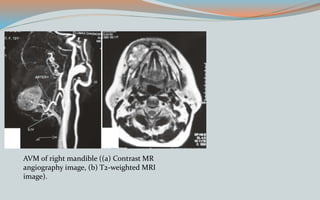

AVM of right mandible ((a) Contrast MR

angiography image, (b) T2-weighted MRI

image).